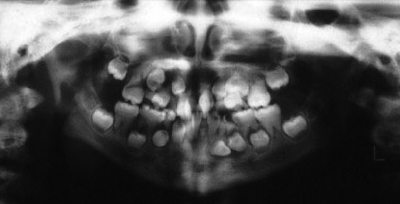

10歳の女児。永久歯の萌出遅延を主訴として来院した。初診時のエックス線写真を別に示す。

疑われるのはどれか。1つ選べ。

a. 骨形成不全症

b. 甲状腺機能低下症

c. 先天性表皮水疱症

d. 鎖骨頭蓋骨異形成症

e. 低フォスファターゼ症